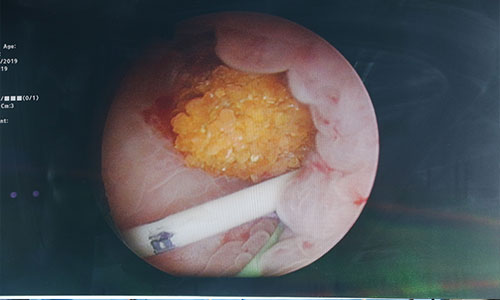

انجام جراحی پیشرفته سنگ کلیه به روش بسته (PCNL) توسط دکتر امیر عباس شه دوست فوق تخصص اندوارولوژی در بیمارستان فوق تخصصی سینا اراک در تاریخ 20 آبان ماه 1398 # این عمل توسط گروه ارولوژی بیمارستان سینا از 2 سال پیش راه اندازی گردیده است . از مزایای این روش ، خروج سنگهای کلیه در یک جلسه و با کمترین برش جراحی و حداقل زمان بستری می باشد .